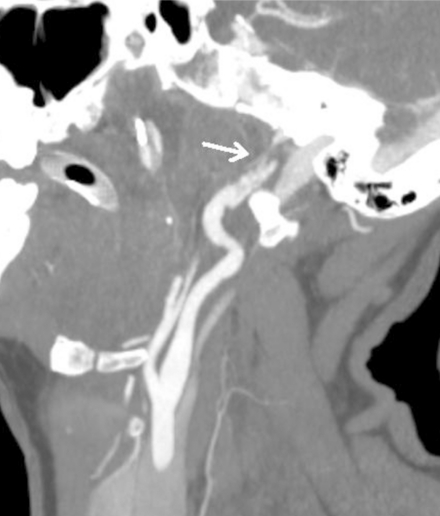

简介:当采用适当的筛查标准时,钝性脑血管损伤(BCVI)在所有钝性创伤中占1-2.7%。相当数量的BCVI患者有潜伏期或无症状期,在此期间,基于适当使用血管造影的治疗干预可能会降低缺血性卒中的风险。方法:病例报告和文献复习。结果:一名42岁的女性从摩托车上摔下来,在急诊室神经系统完好。在非对比计算机断层扫描(CT)上发现累及颈椎横孔的骨折,但未进行BCVI血管造影筛查。随后,她患上了缺血性中风,导致严重残疾。本文回顾了针对BCVI筛查标准的使用及后续治疗的已发表研究。结论:BCVI可导致缺血性脑卒中显著的发病率和死亡率。BCVI与缺血性脑卒中的发生之间往往有一段潜伏期。特定的危险因素可用于确定需要导管或CT血管造影筛查的患者。抗血栓药物治疗是BCVI的主要治疗方法,可以降低缺血性卒中的发生率。钝性创伤患者无症状BCVI的识别和治疗可以预防缺血性脑卒中的主要是年轻人群。

Introduction: Blunt cerebrovascular injury (BCVI) is found in 1-2.7% of all blunt trauma when appropriate screening criteria are employed. A significant number of patients with BCVI have a latent, or asymptomatic period, in which therapeutic intervention based on the appropriate use of angiographic imaging may decrease the risk of an ischemic stroke. Methods: Case report and review of literature. Results: A 42 year old woman suffered a fall off a motorcycle and was neurologically intact in the emergency room. Fractures involving the transverse foramen of cervical vertebrae were found on non-contrast Computed Tomography (CT) but screening for BCVI with angiographic imaging not performed. She subsequently suffered an ischemic stroke resulting in significant disability. Published studies that address the use of screening criteria for BCVI and subsequent management are reviewed. Conclusion: BCVI results in significant morbidity and mortality attributable to ischemic stroke. There is often a latent period between BCVI and occurrence of ischemic stroke. Specific risk factors can be used to identify patients requiring screening with catheter or CT angiography. Treatment with antithrombotic agents is the mainstay of treatment of BCVI and may reduce the rate of ischemic stroke. Identification and treatment of asymptomatic BCVI in blunt trauma patients may prevent ischemic stroke in a predominantly young population.